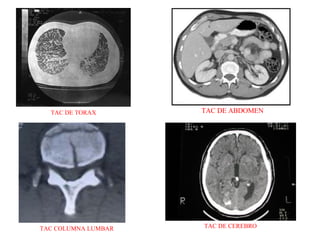

EL ESTUDIO Para comenzar el estudio necesitamos identificar, no solo al paciente, sino también la zona anatómica que queremos estudiar. Para todo esto el radiólogo nos dará la programación, es decir, la zona correcta que tenemos que cortar, los grosores e intervalos de corte, la administración o no del contraste y el tipo. Una vez que nos aseguramos que coincidan tanto los datos del paciente como el estudio requerido, pasamos a la colocación del paciente en la camilla. Le explicamos lo que vamos s hacer e introducimos los datos en la consola de operaciones: -Numero de identificación del estudio  -Sexo -El del paciente  -Procedencia -Apellido y nombres  -Tipo de estudio -Edad  -Características y parámetros del estudio  PLANOS El tomógrafo va a realizar cortes  axiales  y por medio de la angulacion del gantry y determinadas posiciones del paciente, también cortes  coronales . Los planos de corte mas comúnmente utilizados, lo s cuales en algún caso , pueden variar son: CRÁNEO:  AXIAL - SILLA TURCA:  CORONAL - SENOS PARANASALES:  AXIAL o CORONAL ORBITAS:  AXIAL o CORONAL - PEÑASCOS:  IGUAL - CAVUN, LARINGE:  AXIAL TORAX:  AXIAL - COL CERVICAL:  AXIAL - COL DORSAL:  AXIAL-  ABDOMEN:  AXIAL COL LUMBAR:  AXIAL - PELVIS:  AXIAL - CADERAS:  AXIAL.

TAC DE TORAX TAC DE ABDOMEN TAC COLUMNA LUMBAR TAC DE CEREBRO